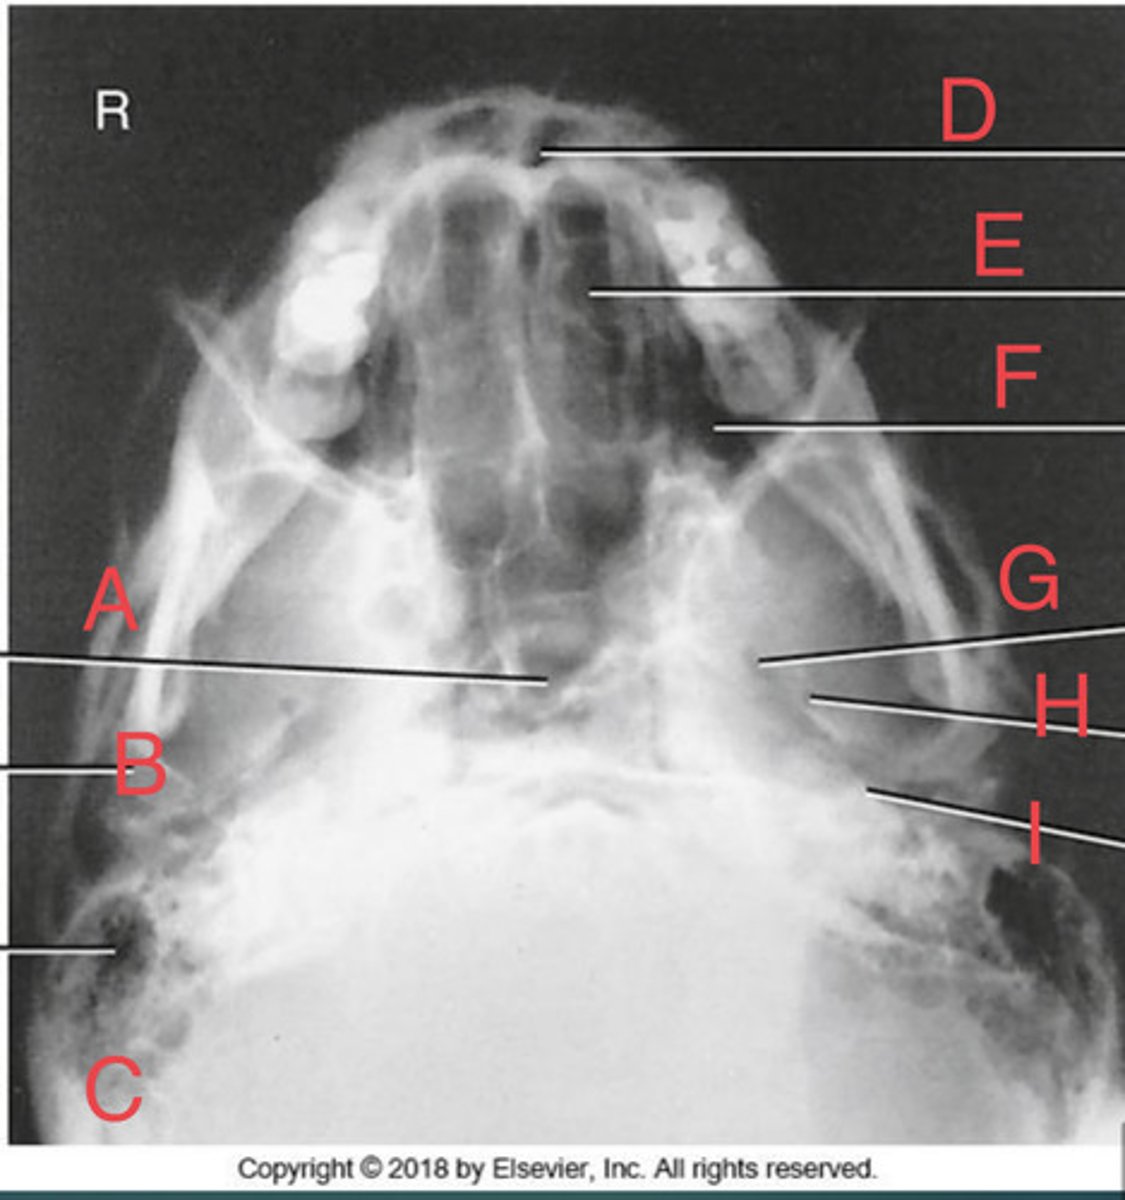

SMV sinuses

What position?

Sphenoid sinus of sphenoid bone

A.

R mandibular condyle of mandible

B.

R Mastoid air cells of temporal bone

C.

Nasal fossa

D.

L. Ethmoid sinus of ethmoid bone

E.

L maxillary sinus of maxilla

F.

L foramen ovale of sphenoid bone

G.

foramen spinosum of sphenoid bone

H.